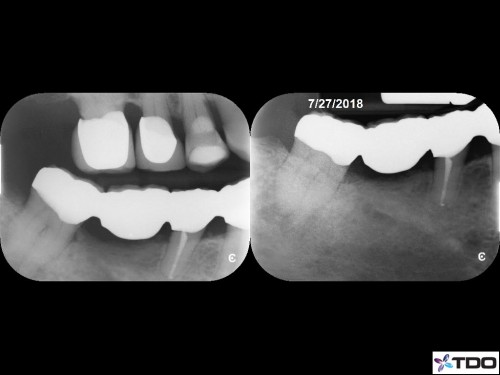

#31 Purulent drainage 3v 1

66 yof

ER patient. Left drainage hole and medicated/closed 3 days later.

Asymptomatic at the complete appt 20 days later.